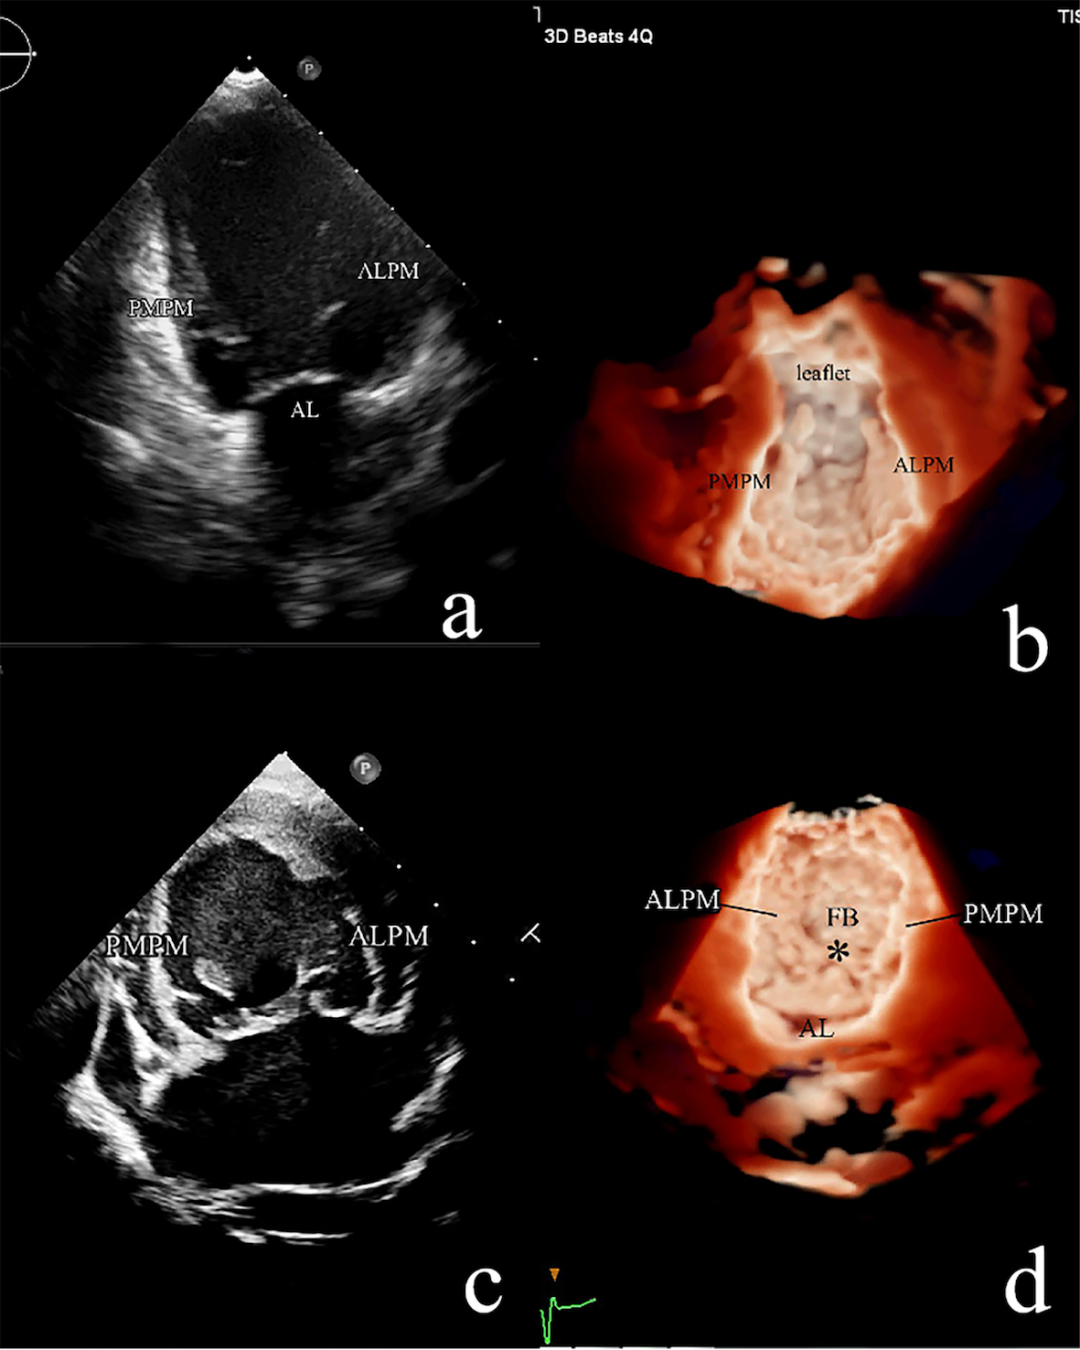

1. 共纳入207例患者,86例患儿超声诊断为UCMV(41.6%),其中77例接受了二尖瓣成形手术:75例通过手术明确诊断为UCMV(40.5%),1例患儿诊断为二尖瓣脱垂,1例患儿为功能性MR。121例患儿超声诊断其他类型的二尖瓣病变,其中110例进行了二尖瓣成形或置换手术。对于UCMV病变的诊断超声和手术结果呈现较高的一致性(kappa = 0.857, p < 0.001)。下图分别显示三种类型的UCMV的二维和三维超声心动图以及术中探查的结果。

UCMV疾病谱涵盖了二尖瓣拱廊及其一系列相关的非典型病变(如半二尖瓣拱廊、部分吊床样二尖瓣),其胚胎学机制被认为是二尖瓣在胶原化腱索衰减和延长之前发育停滞的结果。根据病变腱索的情况及是否合并MS,将UCMV分为三型,从I型到III型病变的程度是逐渐加重的,这表明二尖瓣腱索发育停止发生的时间越来越早,因此,III型患者的二尖瓣功能障碍更重,手术预后更差。典型二尖瓣拱廊的解剖与UCMV III型以及一部分II型是相似的。拱廊由两组肥厚的乳头肌和纤维桥组成,纤维桥由二尖瓣前叶增厚的下缘和中间的腱索组成。纤维桥在某些患者中并不典型,因此不作为UCMV的诊断标准。典型的先天性MS归属于III型UCMV。UCMV的另一个显著特点是所有的类型中ALCT都与腱索分布不良相关,而不存在PMCT单独病变的情况,可能是由于PMCT的腱索发育较ALCT完成的更早。UCMV I型的解剖特点和既往文献中所描述的降落伞样二尖瓣的病变是非常相似的。因此,我们认为,UCMV构成了儿童二尖瓣发育不良的主要发病机制。肥大延长的乳头肌和明显缩短或缺失的腱索,导致瓣叶的移位,瓣叶运动受限、对合缘较少从而引起二尖瓣返流或狭窄。